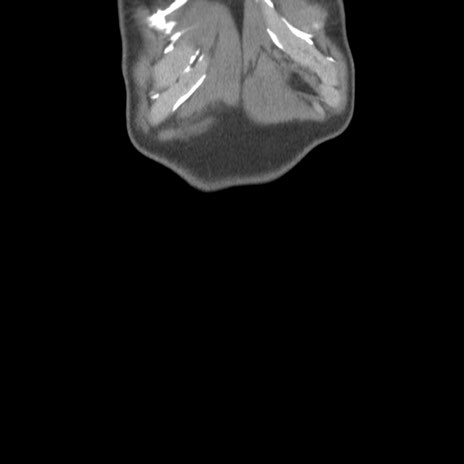

横断像